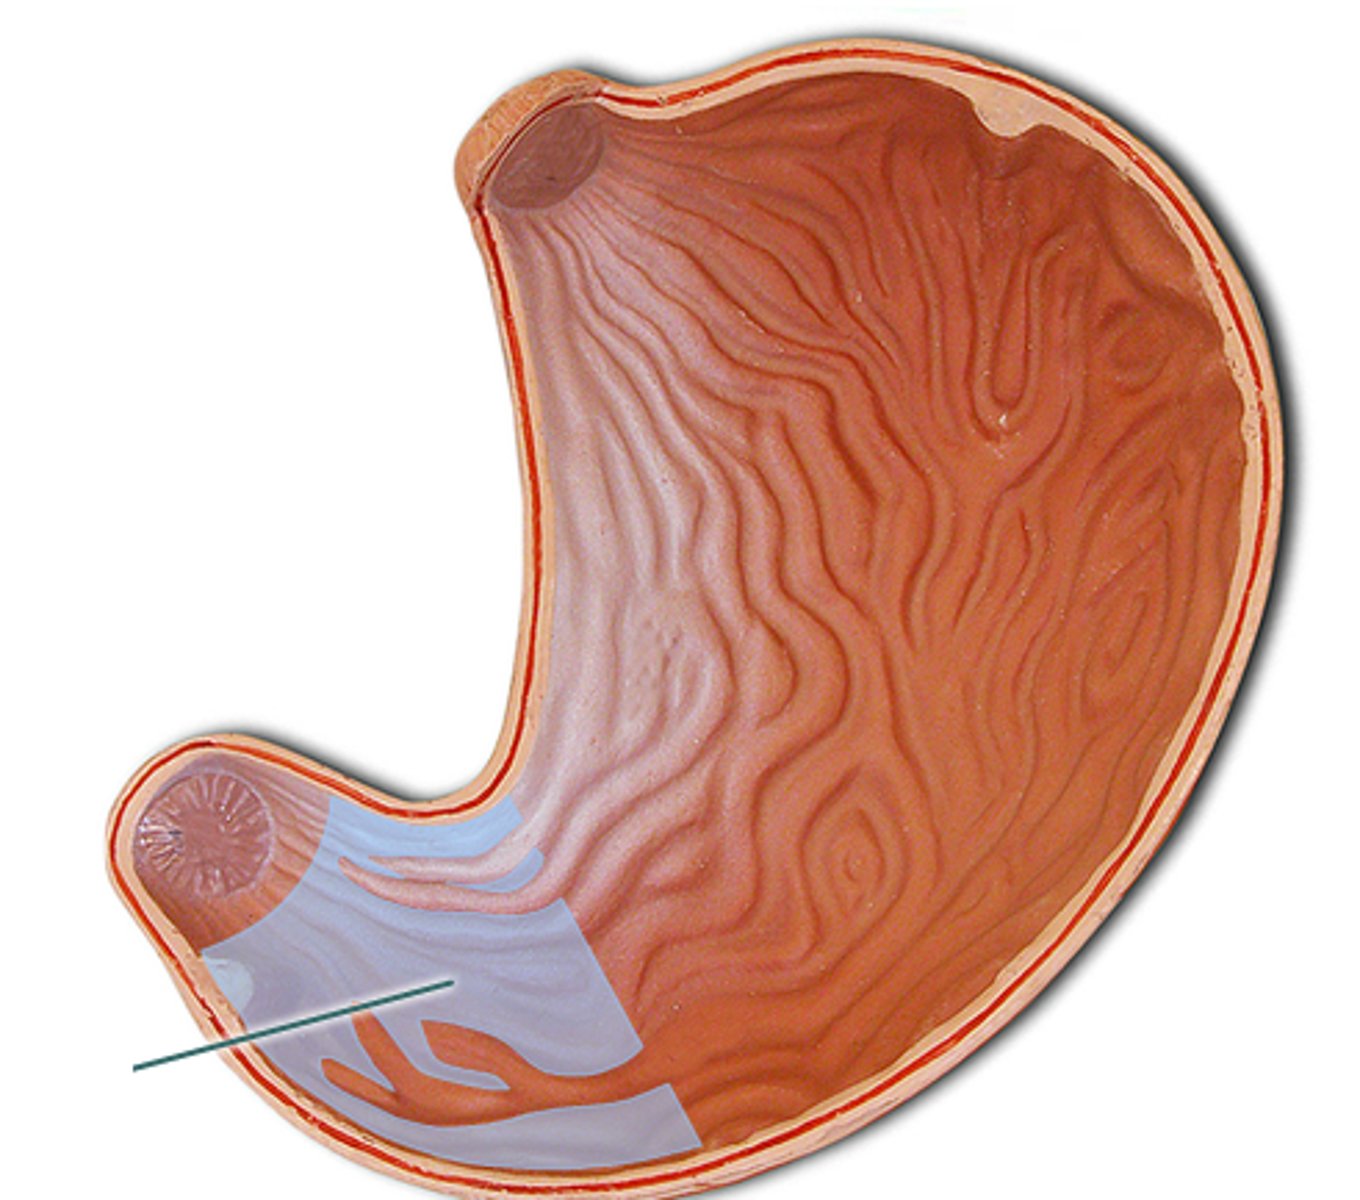

pyloric sphincter